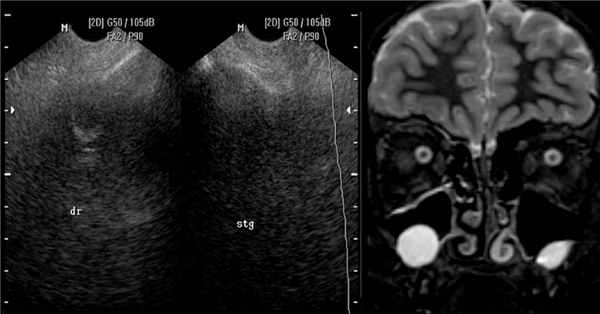

Кисты верхнечелюстных пазух (ВЧП) — частая находка при рентгенологических исследованиях околоносовых пазух (ОНП). Они составляют от 89,5 до 92,7% всех кист, локализованных в ОНП [1—3]. Частота обнаружения кист ВЧП зависит от способа визуализации и колеблется в широких пределах — от 1,4 до 35,6% [1], в среднем кисты ВЧП выявляются у 21,6% обследованных [4, 5]. Наиболее информативными методами обнаружения кист ОНП являются компьютерная томография (КТ) и магнитно-резонансная томография (МРТ), которые обнаруживают их примерно с одинаковой точностью [6].

Наиболее масштабное из приведенных в таблице исследований — работа I. Moon и соавт. [2] — описывает динамику изменения размеров кист ОНП у 133 пациентов, которым производили МРТ головного мозга с целью профилактического исследования более 2 раз с периодом наблюдения не менее 24 мес.

В среднем период наблюдения составил 40,38±16,09 мес (от 24,0 до 109,8 мес). У 119 из 133 больных при первичном исследовании были обнаружены кисты в ВЧП размером от 13,35±9,22 до 15,49±6,94 мм. При наблюдении от 24 до 36 мес размеры кист остались без изменения у 73% пациентов, у 22% уменьшились или исчезли и лишь в 5% случаев отмечалось увеличение размера кисты. В дальнейшем (более 48 мес) изменение размеров кист происходило в большем числе случаев: неизменными остались размеры 42% кист, 43% уменьшились или исчезли, в 15% случаев кисты увеличились.